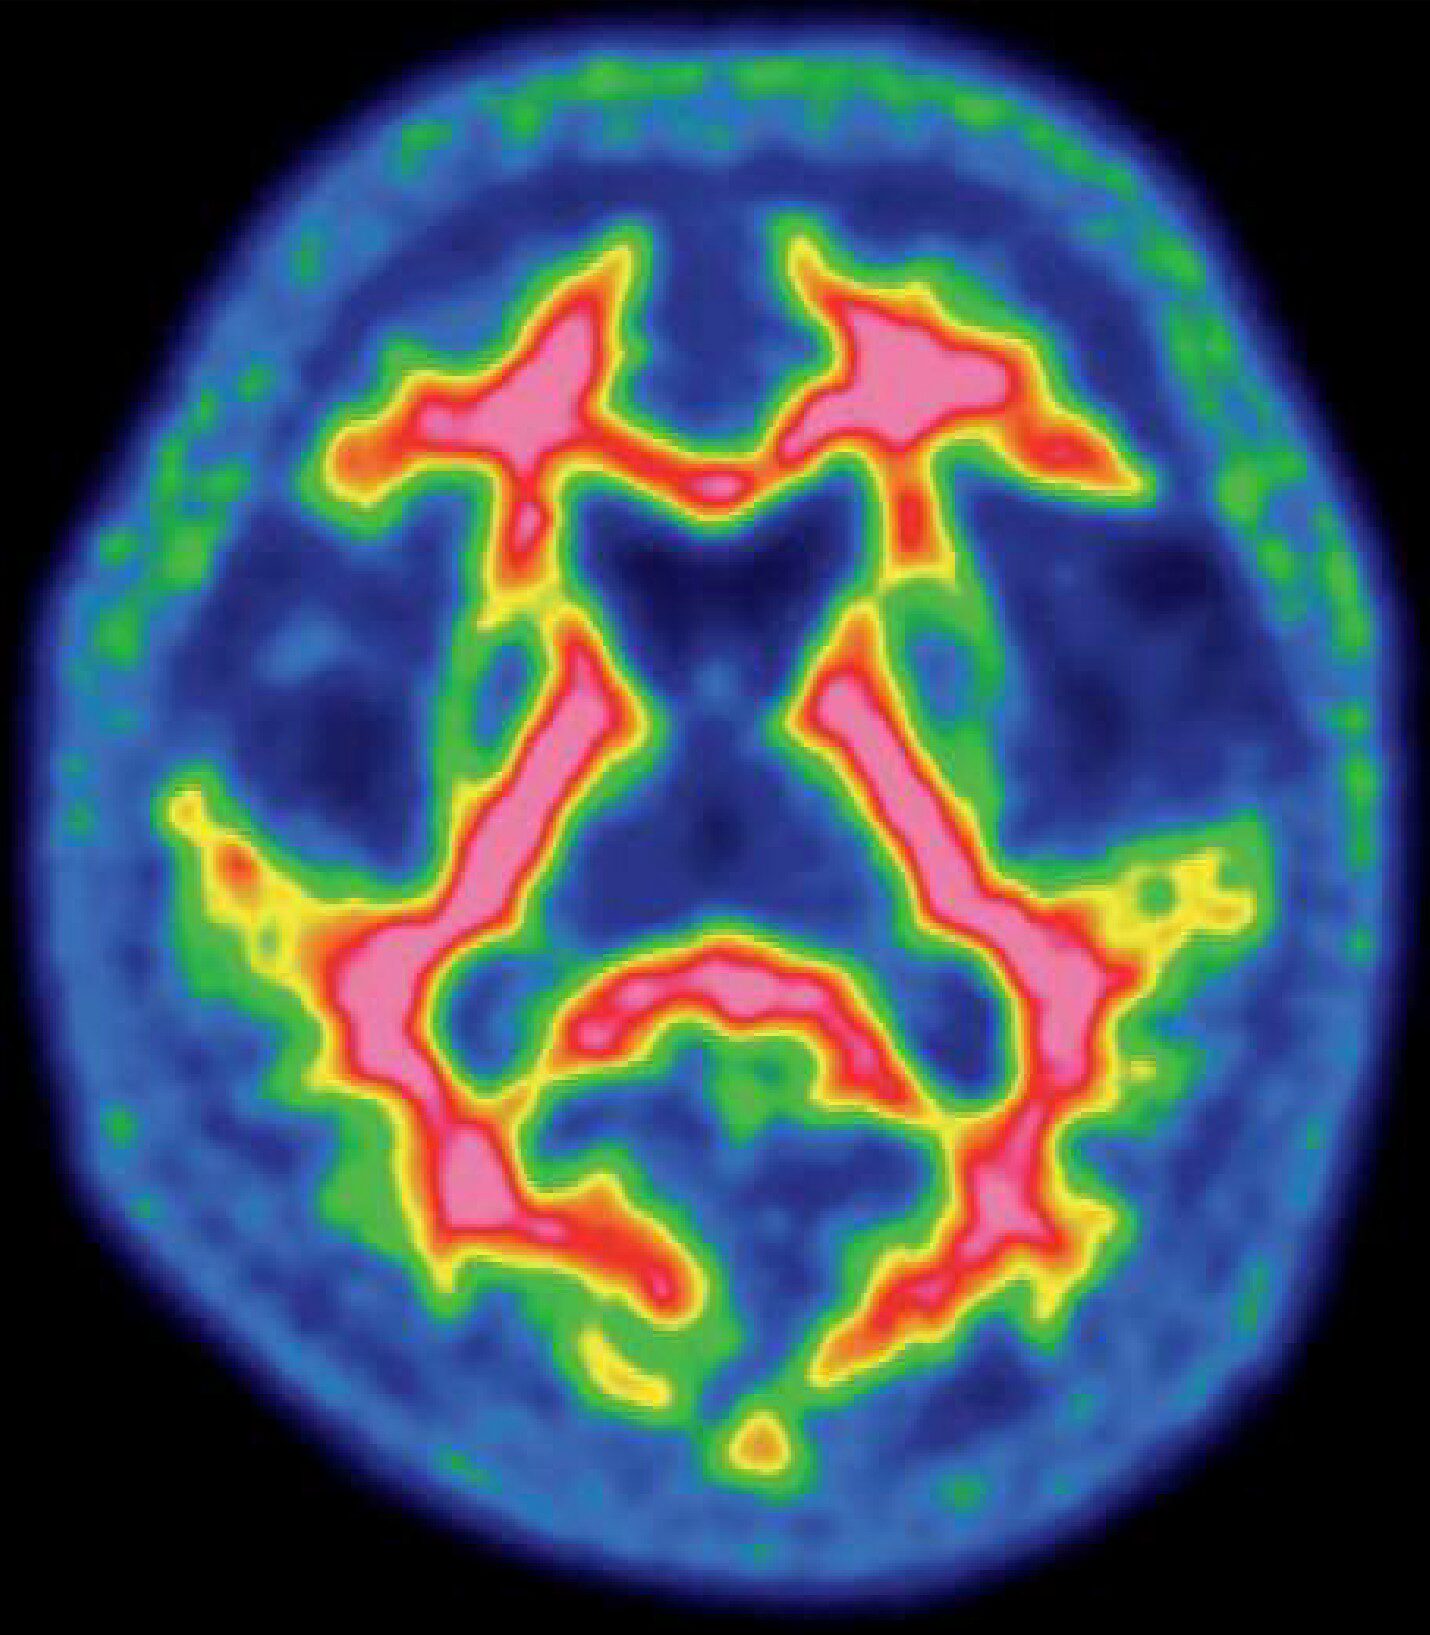

Q16 / 20核医学検査技術学

正常の脳核医学画像(別冊No.6)を別に示す。使用した放射性医薬品はどれか。

- 1123I-IMP

- 218F-FDG

- 315O-CO2ガス

- 4123I-イオフルパン

- 518F-フルテメタモル